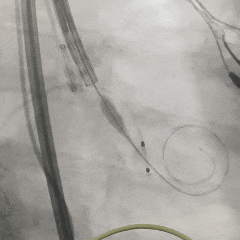

手术过程

左冠造影检查

20mm球囊扩张,无腰无漏,球囊轻微滑动

TF23瓣膜0位初始释放

瓣膜第一次展开造影评估,位置偏浅,回收调整

第二次释放造影评估

瓣膜深度可,展开良好,无瓣周漏

瓣膜解锁后造影评估

瓣膜深度合适形态良好,冠脉灌注良好,无瓣周漏

最终多角度观察瓣膜形态,瓣膜展开良好

超声测量流速1.5m/s,手术结束